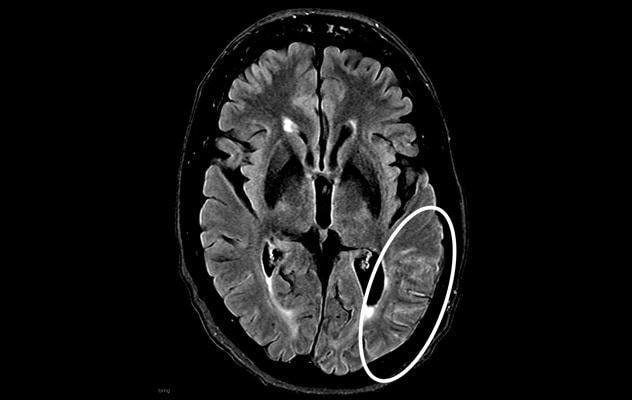

Moderate ARIA-E Moderate ARIA-E

Axial fluid-attenuated inversion recovery MRI in the same patient shows hyperintense sulcal effusion involving the left temporal region (white circle) — indicating moderate ARIA-edema (ARIA-E). Antiamyloid therapy was discontinued after imaging.